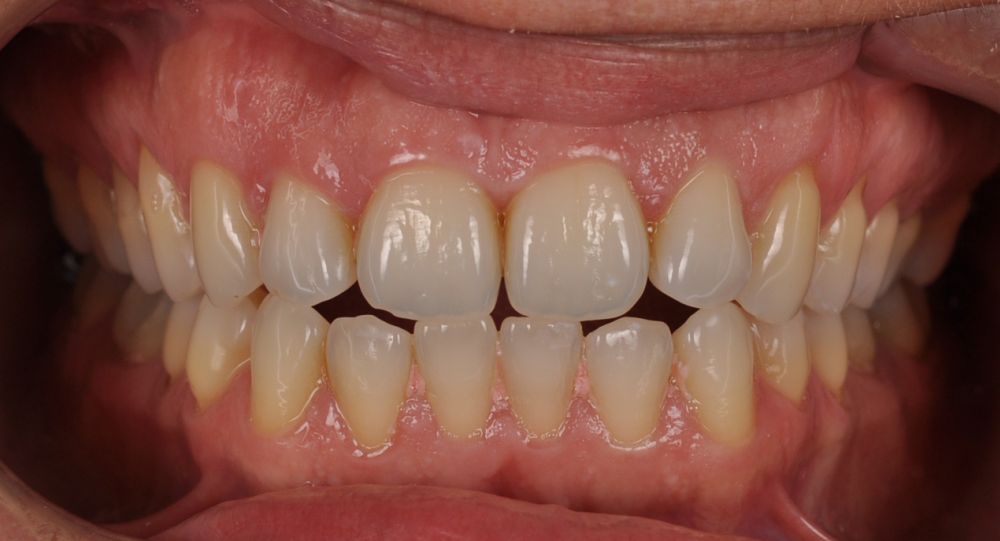

El día de la colocación de las estructuras, se arenó el interior de las coronas dentosoportadas con óxido de aluminio de 50 m y fueron cementadas con cemento de resina Multilink Ò. El puente implantosoportado se atornilló al torque indicado (20Nw) (Figuras 14, 15, 16 y 17).

En enero de 2021, el puente implantosoportado fue atornillado con un torque controlado (20 Nw), y las coronas dentosoportadas cementadas con éxito. La paciente refirió una notable mejoría en la función masticatoria, fonación y estética facial, manifestando un alto grado de satisfacción.

En el seguimiento a 4 años tras la colocación de la prótesis definitiva, no se observaron complicaciones mecánicas ni biológicas. La paciente continúa libre de enfermedad y con una correcta adaptación al tratamiento rehabilitador implantosoportado (Figura 18).